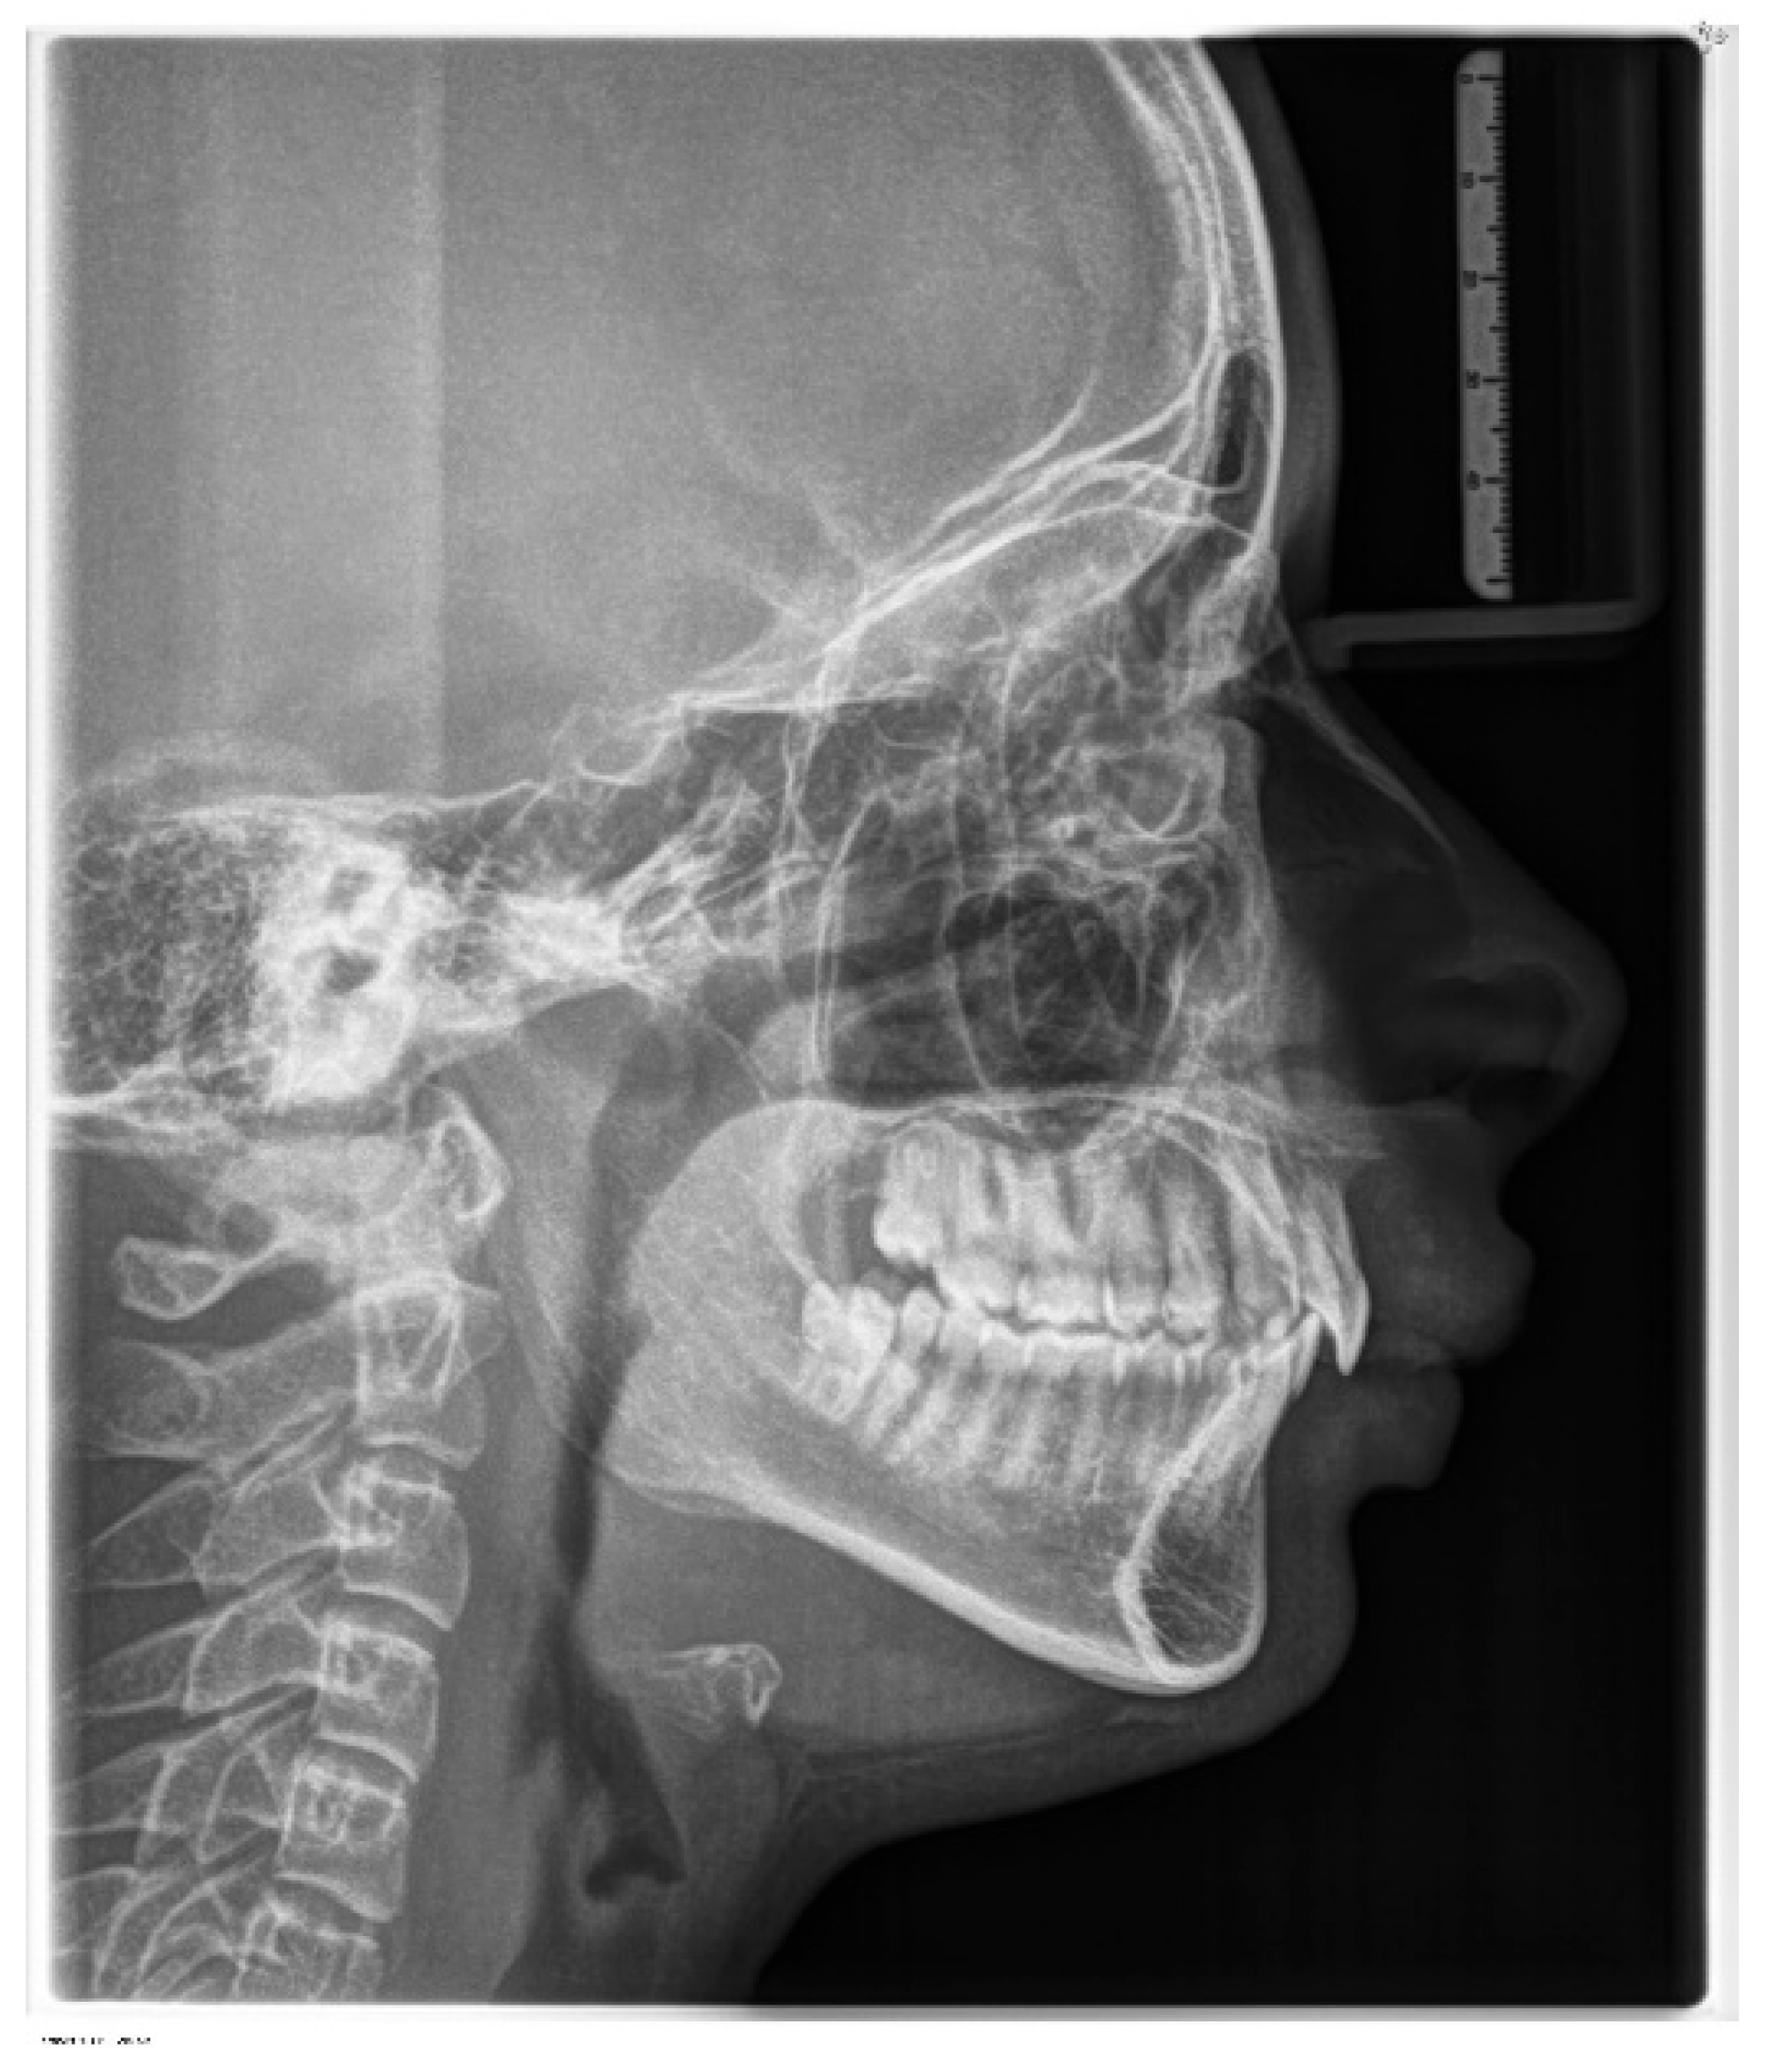

2.1. Diagnosis and Aetiology

2.2. Treatment Objectives